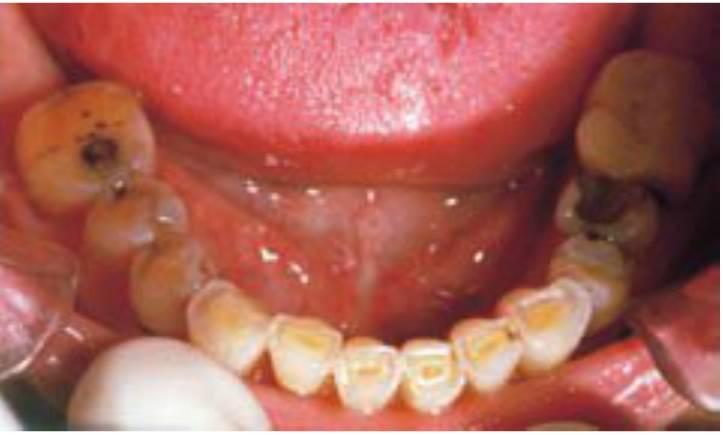

Afortunadamente, existen muchos signos clínicos que avisan de un excesivo rechinamiento. Los signos del bruxismo incluyen un aumento del tamaño de los músculos masetero y temporal (estos músculos y el pterigoideo externo pueden presentar molestias), desviación del maxilar inferior en la apertura, disminución de la apertura oclusal, aumento de la movilidad dentaria, desgaste cervical de los dientes, fractura dentaria o de las restauraciones y descementado de coronas o de prótesis fija. Sin embargo, el método de diagnóstico mejor y más sencillo del bruxismo es el examen del desgaste dentario. No solo es la forma más fácil de determinar el bruxismo en cada paciente individual, sino que permite, además, clasificar esta patología en ausente, suave, moderada y grave (figs. 6-1 a 6-3). Si no existen patrones de desgaste anterior denota una ausencia de bruxismo. En el bruxismo suave aparece un ligero desgaste en dientes anteriores sin que exista un compromiso estético. El bruxismo moderado conlleva facetas de desgaste incisales obvias, pero no hay un patrón de desgaste oclusal posterior. En el bruxismo grave desaparece la guía anterior por el excesivo desgaste y, además, el desgaste dentario posterior es obvio.

A menudo, los pacientes bruxistas repiten movimientos mandibulares, diferentes a los movimientos bordeantes, y tienen una determinada dirección. Como resultado, el desgaste oclusal es muy específico y principalmente en un solo lado de la arcada, o incluso, en solo unos dientes (fig. 6-4).